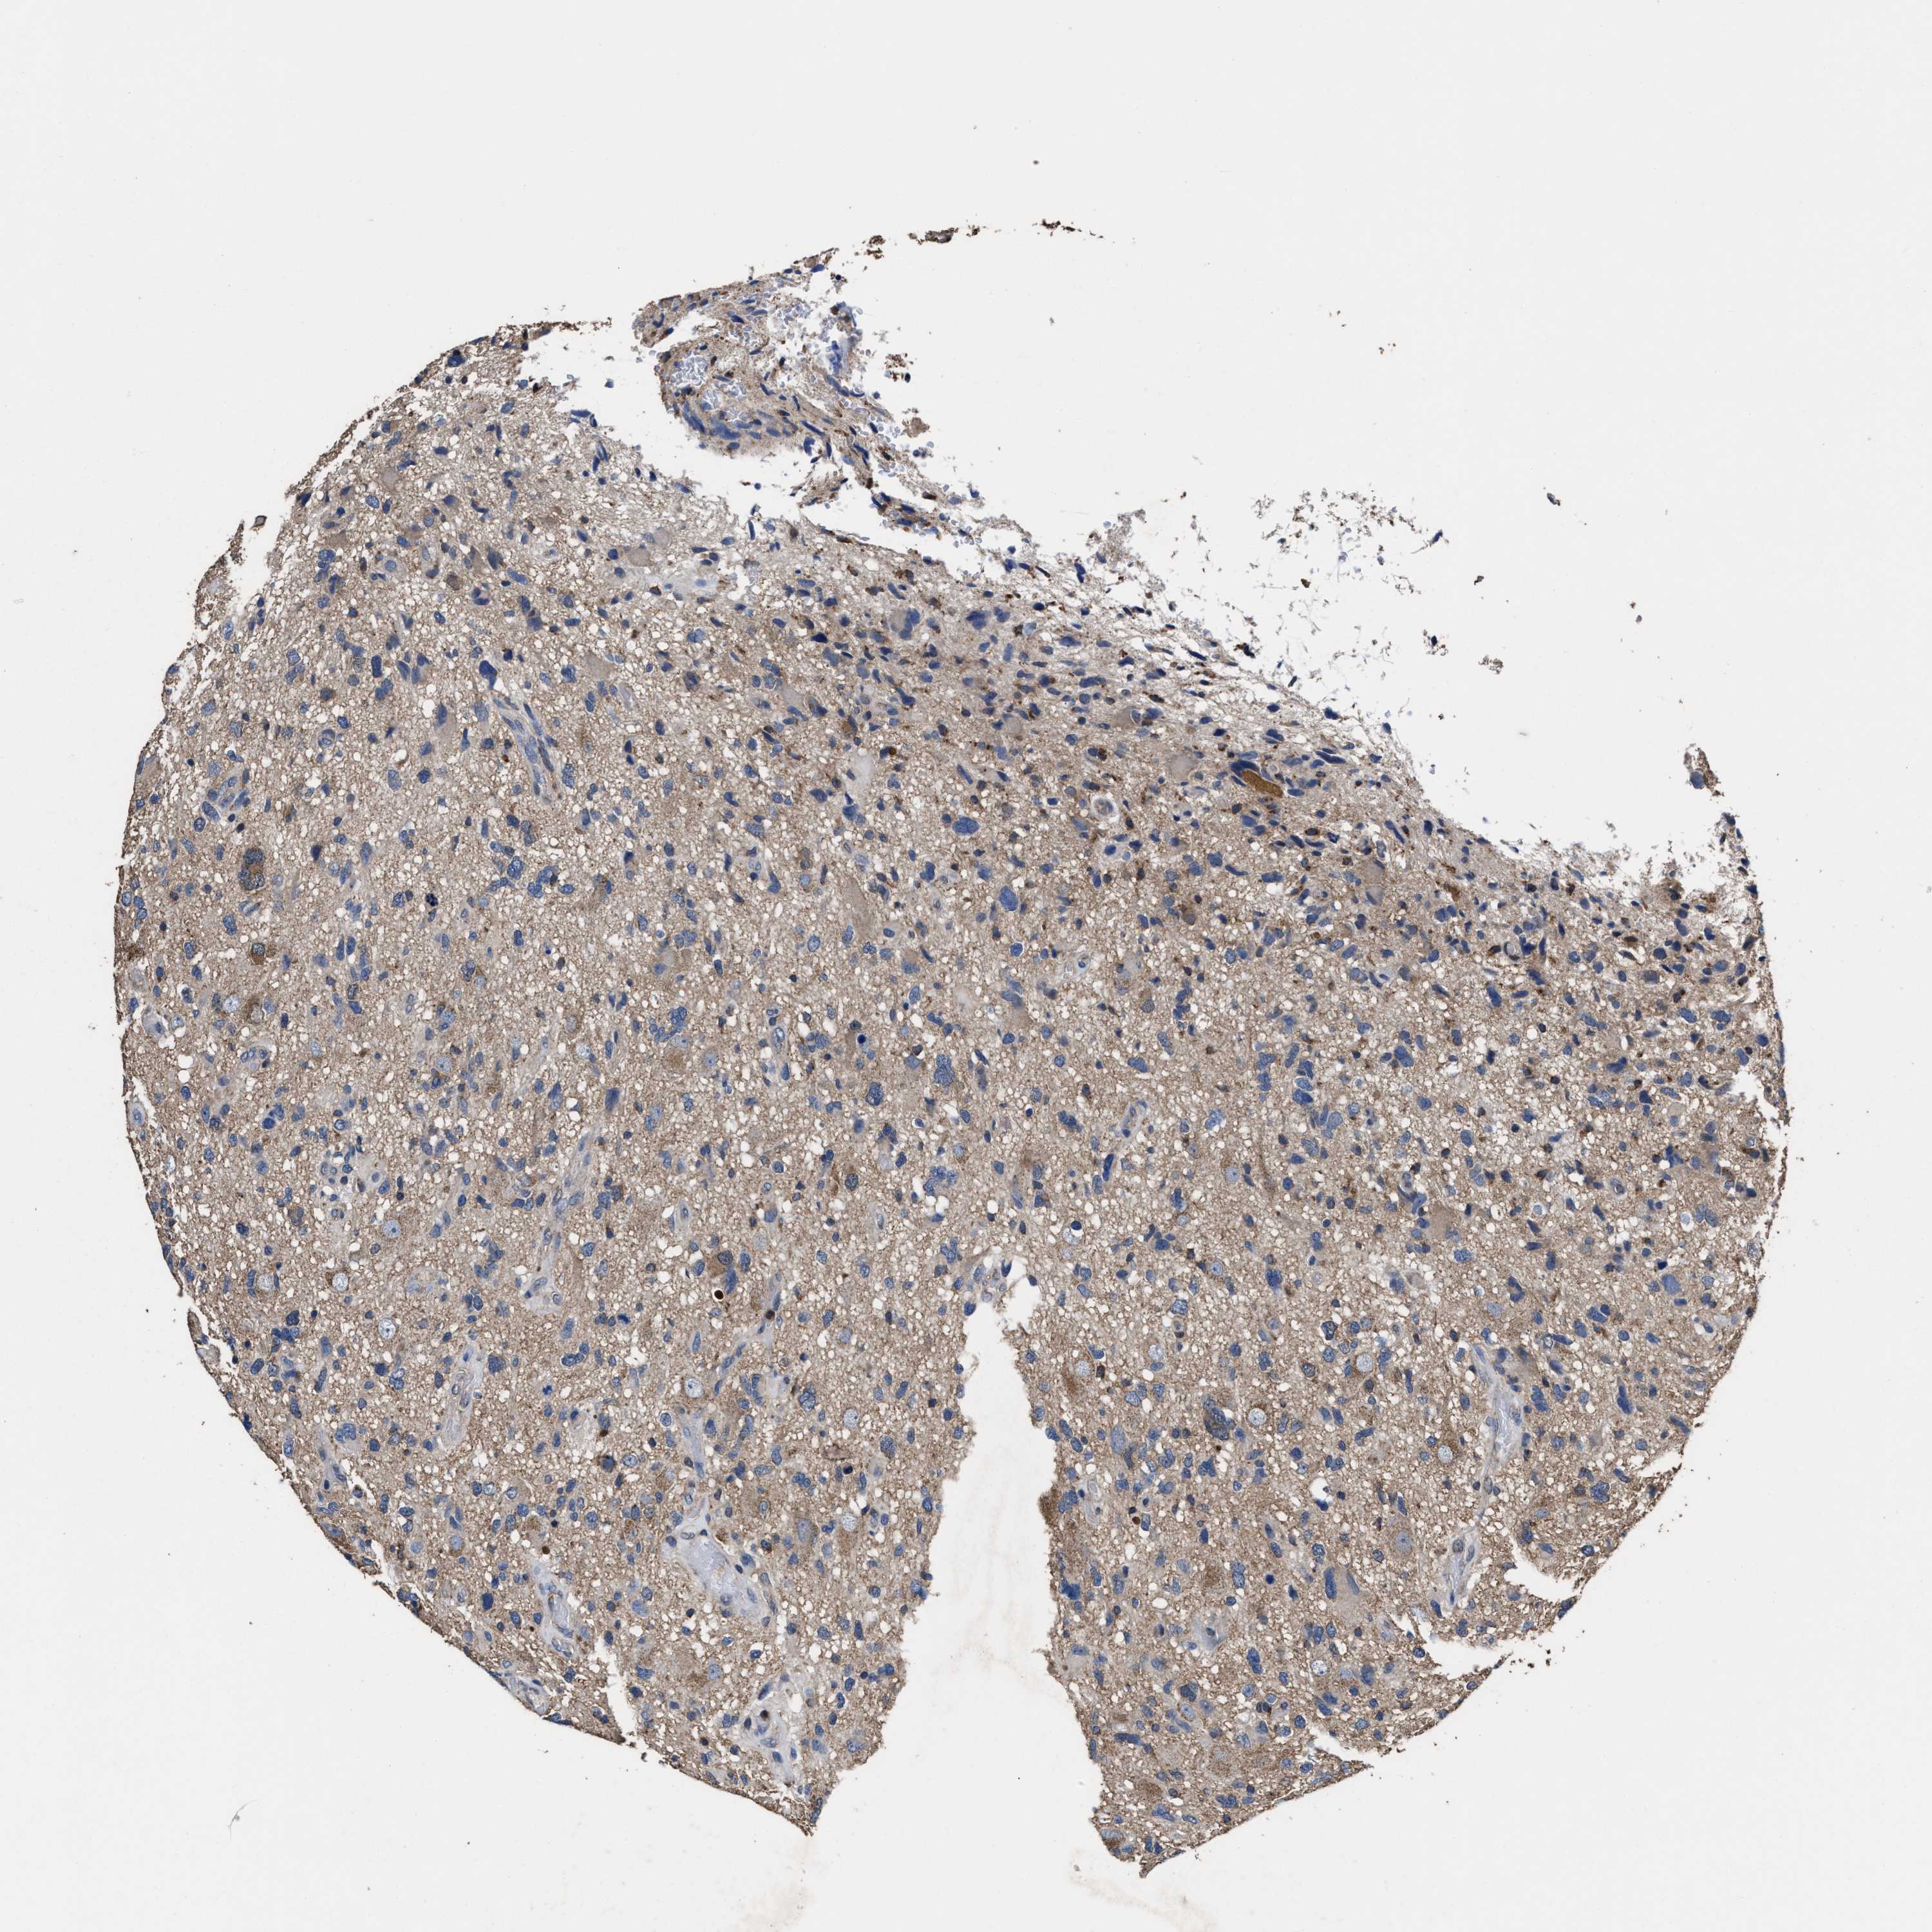

GLIOMA - Protein expressioni

A mouse-over function shows sample information and annotation data. Click on an image to view it in a full screen mode. Samples can be filtered based on level of antibody staining by selecting one or several of the following categories: high, medium, low and not detected. The assay and annotation is described here.

Note that samples used for immunohistochemistry by the Human Protein Atlas do not correspond to samples in the TCGA dataset.

Antibody stainingi

Antibody staining in the annotated cell types in the current human tissue is reported as not detected, low, medium, or high, based on conventional immunohistochemistry profiling in selected tissues. This score is based on the combination of the staining intensity and fraction of stained cells.

Each image is clickable and will lead to virtual microscopy that enables deeper exploration of all samples and also displays staining intensity scores, fraction scores and subcellular localization as well as patient and tissue information for each sample.

HPA022434

HPA022953

HPA022959

HPA028758

CAB007783

Glioma, malignant, High grade

Glioma, malignant, Low grade

Glioblastoma, NOS